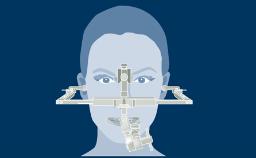

A radiologia é usada em Implantodontia para complementar e confirmar os achados clínicos. As radiografias podem ajudar no diagnóstico, planejamento do tratamento e na revisão de implantes dentários restaurados, em visitas regulares de manutenção. A imagem 3D mostrada aqui demonstra o nível de detalhe que pode ser obtido. No entanto, toda a radiação - incluindo raios-x - acarreta risco de danos aos tecidos e efeitos a longo prazo. Portanto, deve-se considerar os riscos associados à investigação onde a radiografia é planejada, que devem ser equilibrados com os benefícios esperados. Da mesma forma, deve-se considerar uma avaliação das necessidades de diagnóstico e planejamento do caso. A seleção da técnica radiográfica correta deve basear-se no equilíbrio entre as necessidades diagnósticas e o risco.